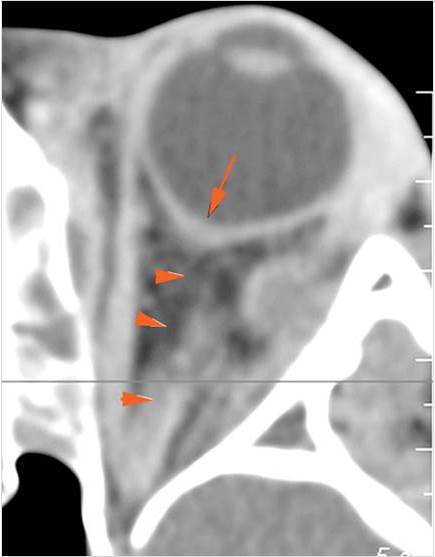

Orbits

The extraconal orbital fat is abnormal. [Yes/No]

There is a subperiosteal abscess or edema along the medial wall, roof or floor of the orbit. [Yes/No]

The extraocular muscles are swollen or otherwise abnormal. [Yes/No]

There is bone erosion along the walls of the orbit. [Yes/No]

The intraconal orbital fat is infiltrated. [Yes/No]

The orbital apex and the superior and inferior orbital fissures are infiltrated. [Yes/No]

The superior and/or inferior ophthalmic veins are dilated or thrombosed. [Yes/No]

Eyes

Proptosis is present. [Yes/No]

The optic nerve is stretched in appearance. [Yes/No]

The posterior aspect of the globe is tented in appearance. [Yes/No]

The uveal scleral margin of the globe is swollen or enhancing abnormally. [Yes/No]

Signs of tension orbit or endophthalmitis are present. [Yes/No]